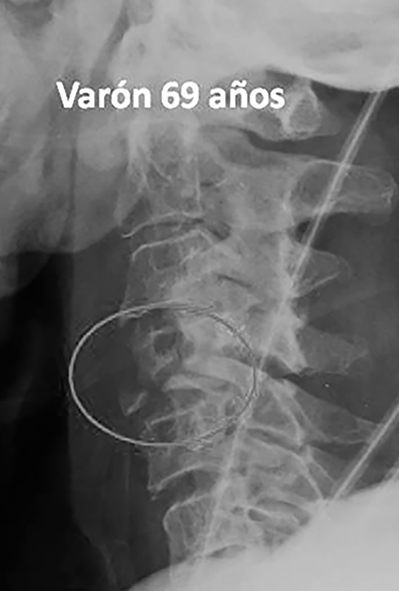

El nivel de lesión cervical fue C4 en el 50% de los casos, C5 en un 37% y C6 en el 13% de los casos. La lesión medular al ingreso fue clasificada en un 75% (6 casos) como ASIA A, 25% (1 caso) ASIA B y un 25% (1 caso) ASIA C. Los dos casos incompletos presentaban un síndrome centromedular de Schneider (Tabla 1).

1 |

H |

64 |

Carretera |

C5 |

Fractura arco posterior atlas |

No |

A |

completa |

conservador |